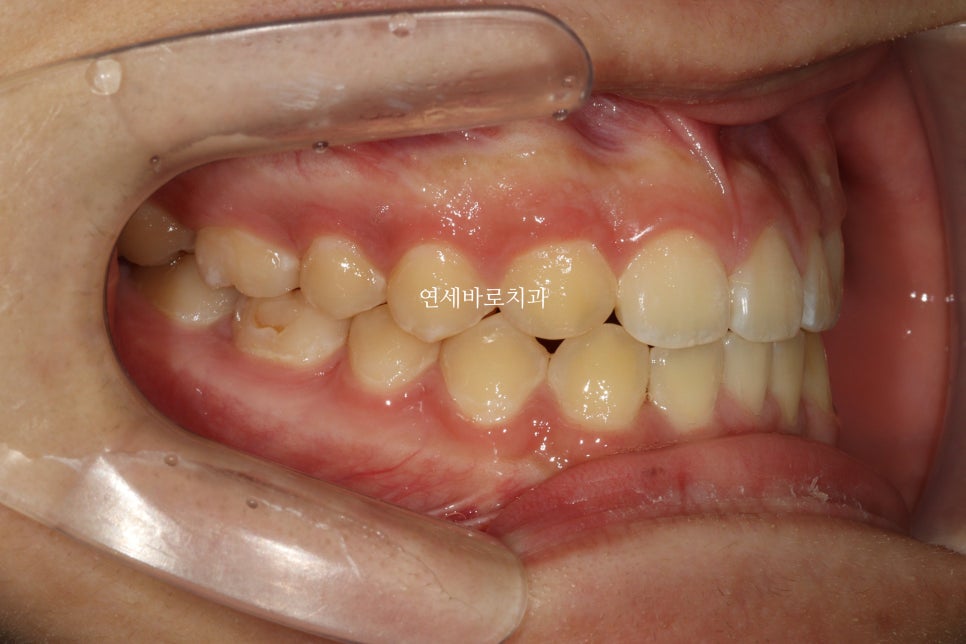

1차교정 후 2차 시작 직전의 모습입니다.

이게 무슨 교정을 한거냐 싶겠지만, 아래쪽은 일부러 남겨둔 상태이며, 위쪽 중심선을 얼굴 중심선과 일치시키며, 공간을 모두 패쇄했습니다.

화살표 치아를 발치했고, 클리피씨를 이용해 치료를 진행했습니다.